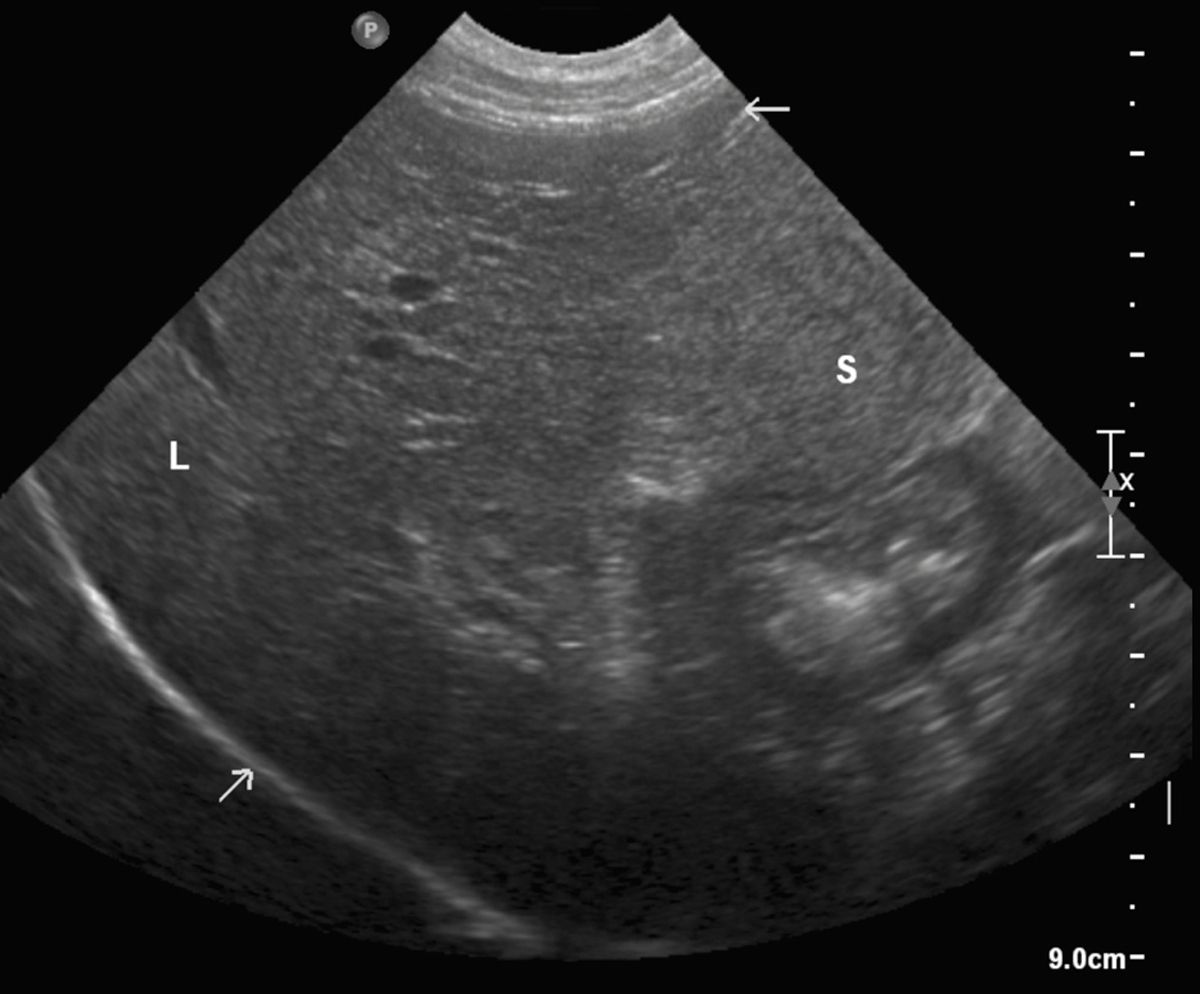

Small Animal Abdominal Ultrasonography, Part 2 Liver and Gallbladder Today's Veterinary Practice Liver Fibrosis Dog Liver fibrosis in young dogs is a condition that may only display subtle signs until your pet’s health has reached a crucial state. Average dose of zinc acetate for a medium dog is 200 mg/day. Liver biopsy is essential for establishing a definitive diagnosis in dogs suspected of having chronic hepatitis. Fibrosis, the formation of fibrous scar tissue in the. Liver Fibrosis Dog.

Small Animal Abdominal Ultrasonography, Part 2 Liver and Gallbladder Today's Veterinary Practice Liver Fibrosis Dog Liver biopsy is essential for establishing a definitive diagnosis in dogs suspected of having chronic hepatitis. Average dose of zinc acetate for a medium dog is 200 mg/day. Fibrosis, the formation of fibrous scar tissue in the liver, can eventually lead to liver cirrhosis. Liver fibrosis in young dogs is a condition that may only display subtle signs until your. Liver Fibrosis Dog.

Liver Fibrosis Ultrasound Liver Fibrosis Dog Cirrhosis of the liver is the generalized (diffuse) formation of scar tissue, associated with regenerative nodules, or masses, and deranged liver architecture. If the fibrosis or it’s underlying. Average dose of zinc acetate for a medium dog is 200 mg/day. Liver biopsy is essential for establishing a definitive diagnosis in dogs suspected of having chronic hepatitis. Cirrhosis is a serious. Liver Fibrosis Dog.

Accuracy of Routine Clinical Ultrasound for Staging of Liver Fibrosis Journal of Clinical Liver Fibrosis Dog However, fibrosis can sometimes be. If the fibrosis or it’s underlying. Cirrhosis of the liver is the generalized (diffuse) formation of scar tissue, associated with regenerative nodules, or masses, and deranged liver architecture. Fibrosis can sometimes be reversed or reduced by proper treatment. Liver biopsy is essential for establishing a definitive diagnosis in dogs suspected of having chronic hepatitis. Liver. Liver Fibrosis Dog.